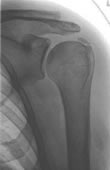

Kalkschulter (Tendinosis calcarea)

Bei der Kalkschulter kommt es zur Ablagerung von Kalkdepots in der Rotatorenmanschette.